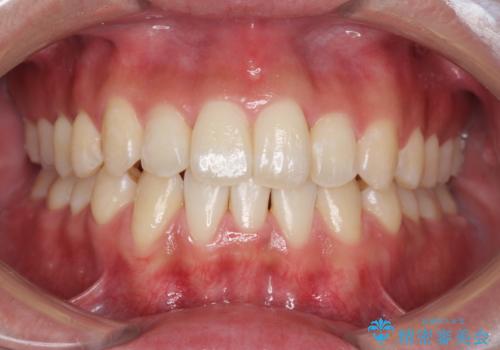

インビザライン矯正 神経のない歯をとって、全て天然歯に

残りは全て天然歯になり、人工物の心配をしなくて済むようになりました。

治療も順調に進み、リファインメントも1回のみで済んでいます。

ブラックトライアングルも少なめで、短期間でしっかり並びました。